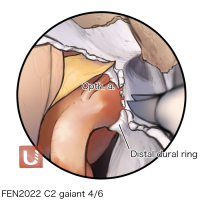

FEN2022シリーズ